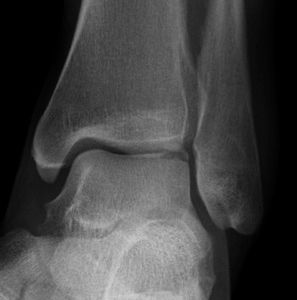

Fracture anterior process of calcaneum